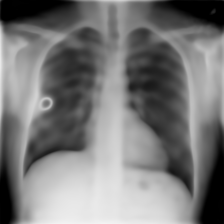

We measure mean squared error (MSE), peak signal-to-noise ratio (PSNR), structural similarity index measure (SSIM), and learned perceptual image patch similarity (LPIPS) [68] and report the results in Table 2. Qualitative examples of the performed reconstruction experiments are shown in Figure 4.

InputRefer to captionRefer to captionRefer to captionRefer to captionRefer to captionRefer to captionRefer to captionRecon.Refer to captionRefer to captionRefer to captionRefer to captionRefer to captionRefer to captionRefer to caption

Figure 4: Input and reconstruction examples from the hold-out test set for (from left to right) chest X-ray [60], chest X-ray [26], retinal OCT [26], fundus camera [30], dermatoscope [9, 58], colon histopathology [24], and cell microscopy [31] images.

While performance is generally better on homogeneous datasets, where redundancies can more effectively be exploited, the proposed method also learns to represent complex inhomogeneous datasets, such as the colon histopathology dataset.444Additional qualitative results can be found in Appendix G.